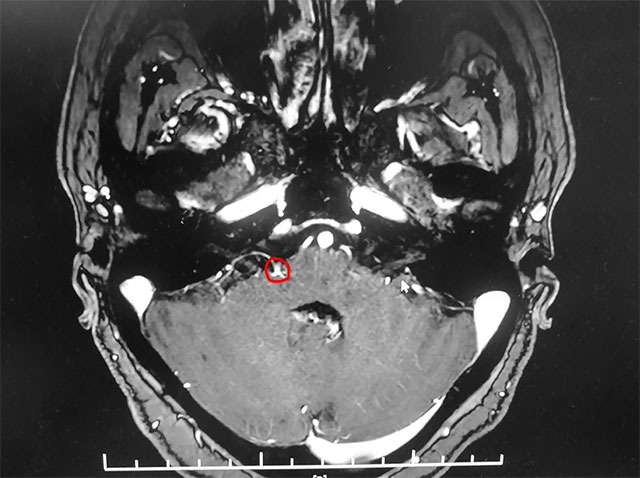

▲ 患者右側(cè)面神經(jīng)與周圍小血管關(guān)系密切

入院后,經(jīng)面神經(jīng)MRTA平掃+增強(qiáng)檢查顯示,患者右側(cè)面神經(jīng)與周圍小血管關(guān)系密切。在對患者病情及影像學(xué)資料進(jìn)行評估,并告知患者及家屬手術(shù)風(fēng)險后,上海藍(lán)十字腦科醫(yī)院神經(jīng)外科主任沈建康教授團(tuán)隊為患者實(shí)施了面神經(jīng)微血管減壓手術(shù)。

術(shù)中,面肌肌電圖檢測到患者眼輪匝肌有自發(fā)性電活動。在顯微鏡下可見,患者的小腦前下動脈和小腦后下動脈與面神經(jīng)接觸密切。沈建康教授小心翼翼地將面神經(jīng)與責(zé)任血管分離,并填入特殊材質(zhì)的墊片。在神經(jīng)電生理監(jiān)測的“保駕護(hù)航”下,避免過重牽拉損傷患者的面神經(jīng)。隨著墊片成功填入,患者面肌肌電圖的自發(fā)性電活動消失了。